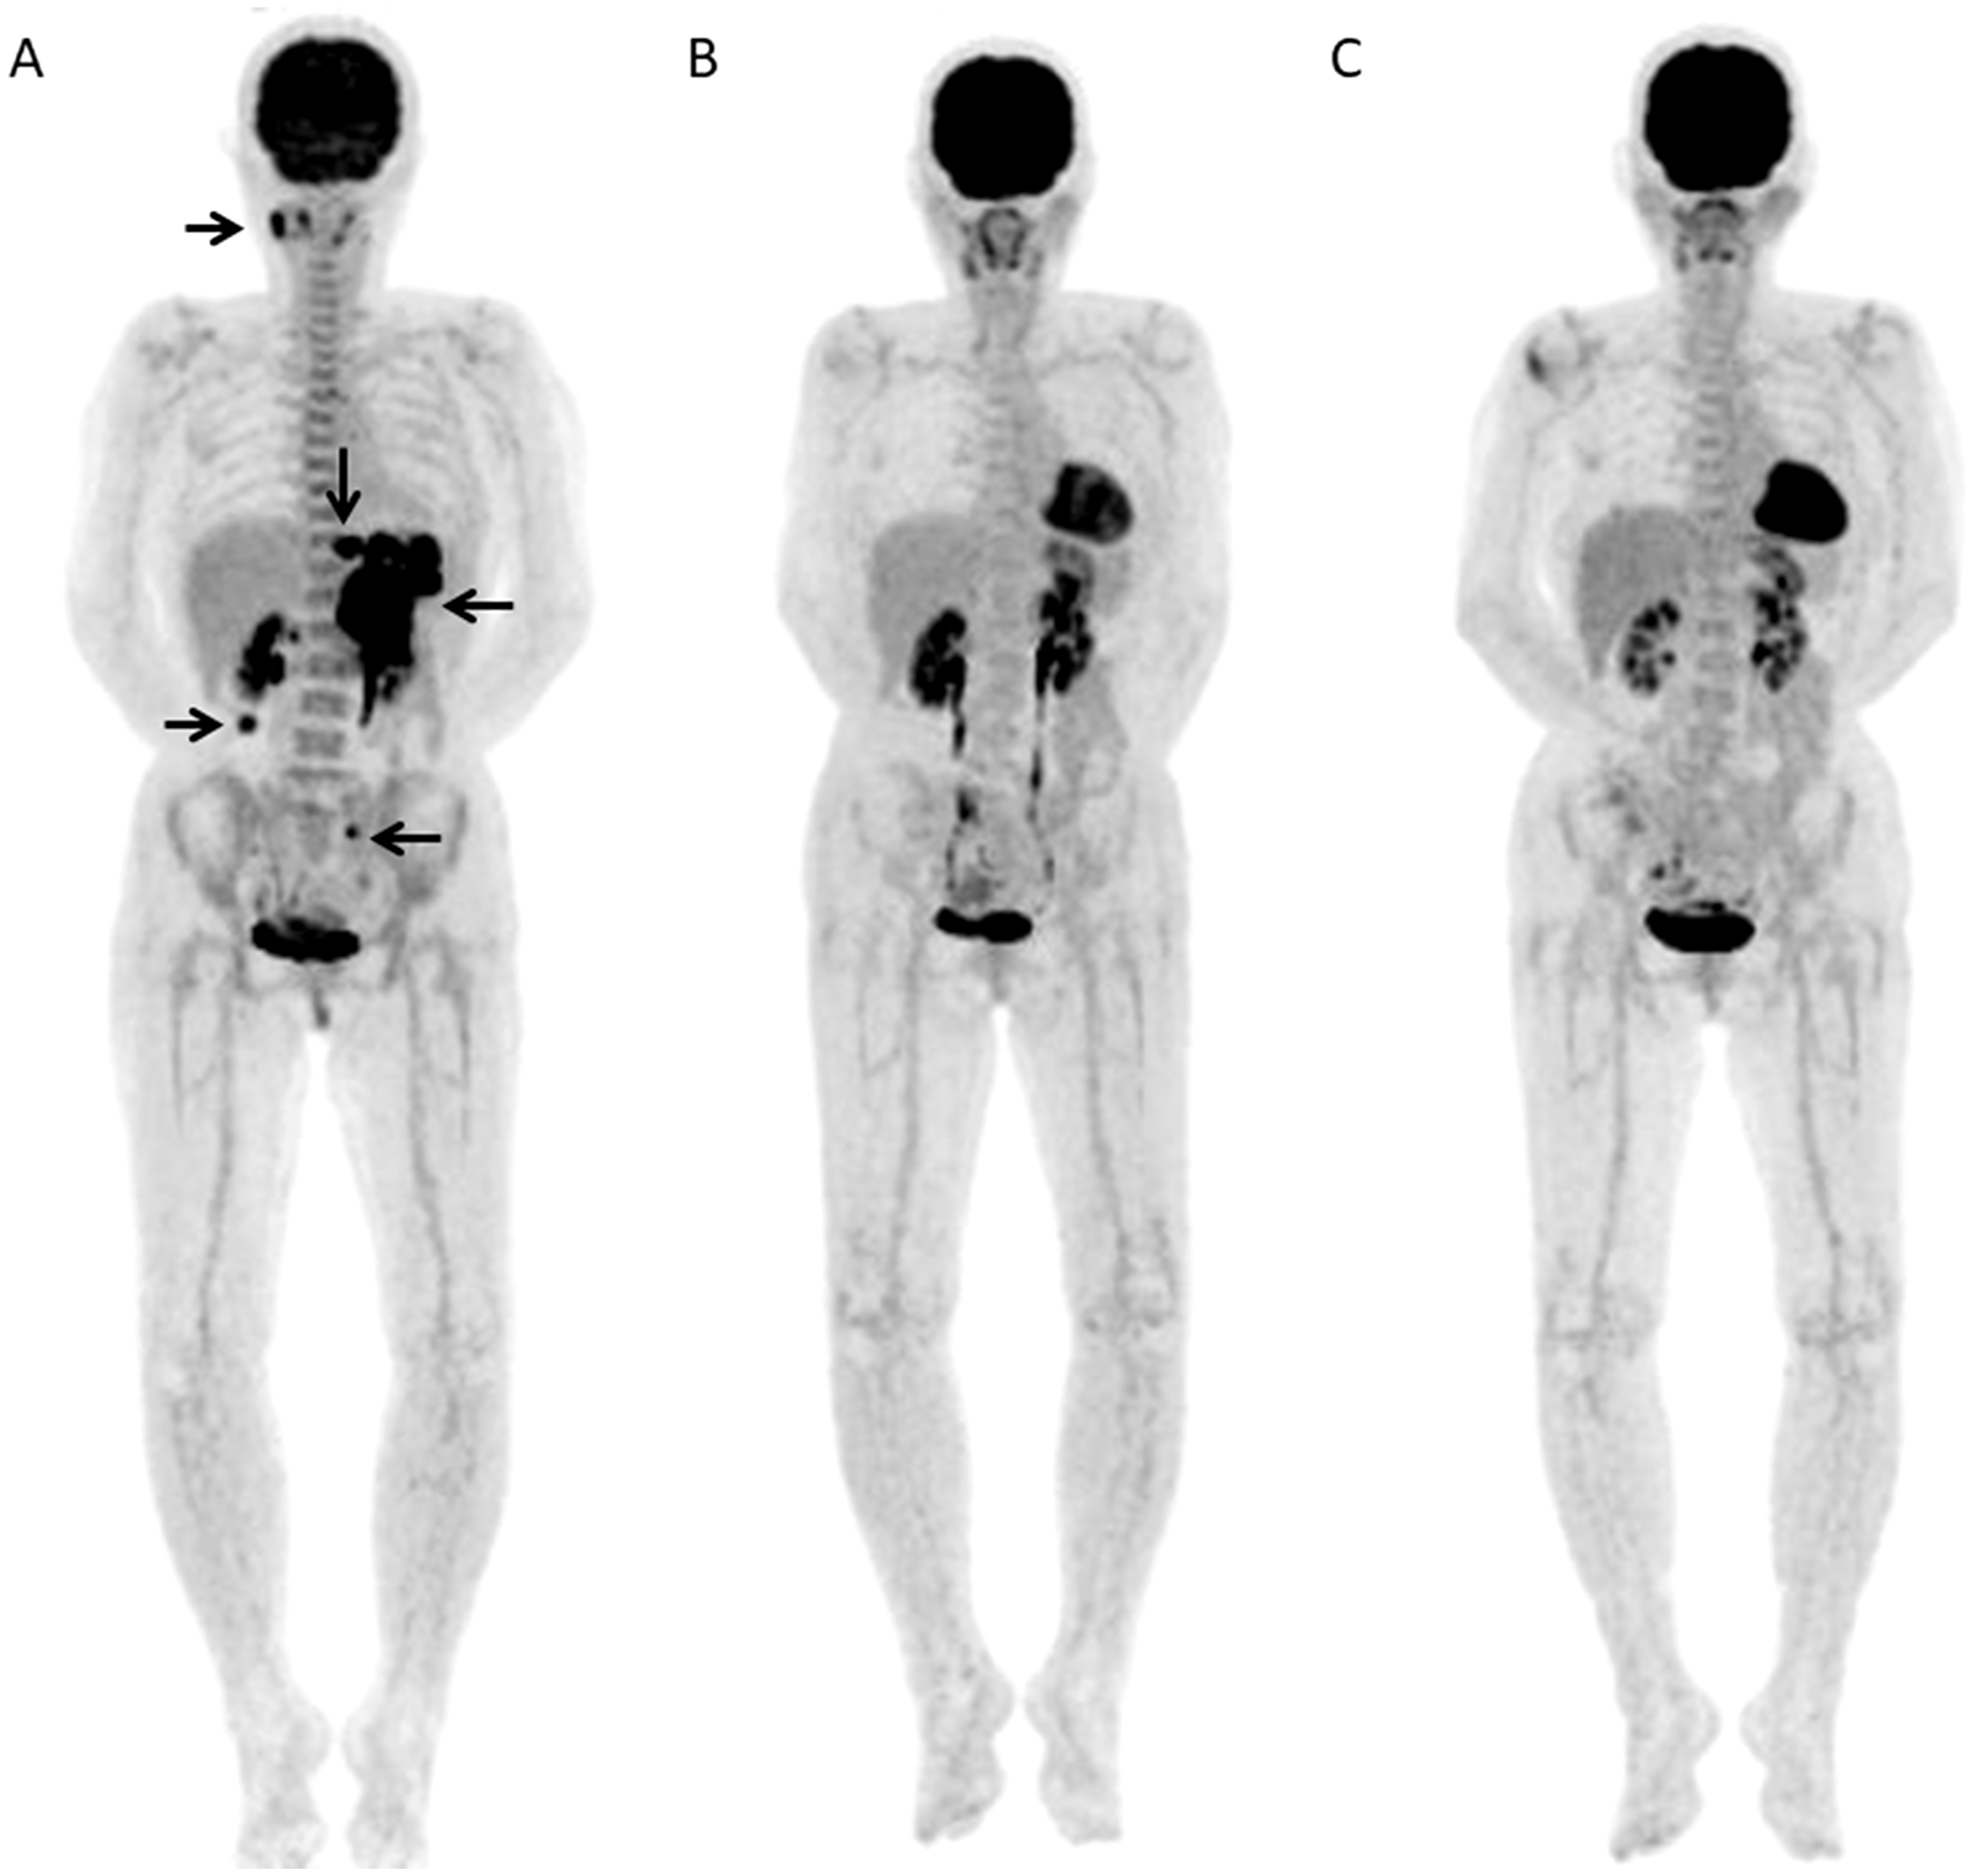

A 80-year-old female with DLBCL received 6 R-CHOP courses and then showed further progression at 0.41 years after the end of chemotherapy

Figure 5: A 80-year-old female with DLBCL received 6 R-CHOP courses and then showed further progression at 0.41 years after the end of chemotherapy. (A) Baseline FDG-PET MIP showed several areas of abnormal FDG uptake in bilateral neck, mediastinum/hilum, and abdomen (arrows). (B) FDG-PET scan MIP after 3 courses of R-CHOP (Interim-PET) showed residual uptake in the mediastinum (arrows). (C) FDG-PET scan MIP after the chemotherapy (End-PET) showed progression of residual uptake in mediastinum and reappearance of abnormal uptake in left hilum (arrows).